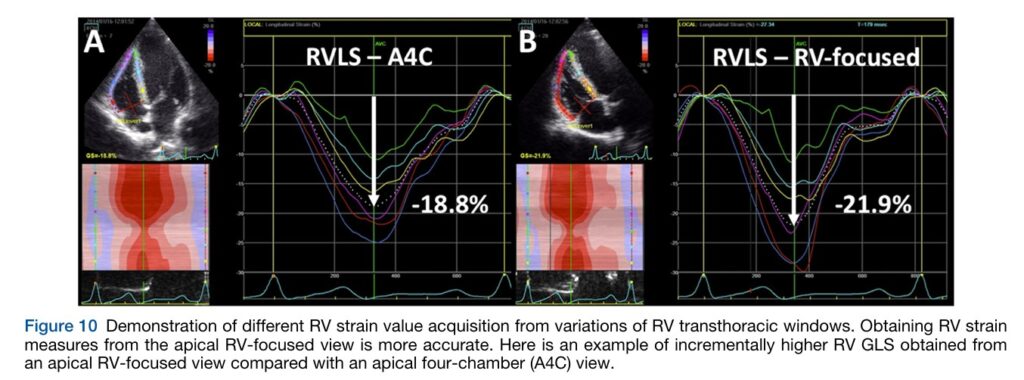

Nesta janela devemos ver o septo interatrial, mas não a valva aórtica ou o seio coronário. É preciso lembrar que o strain longitudinal da parede livre do VD obtido nesta janela habitualmente apresenta maiores valores em relação ao strain obtido na janela apical 4C (ressalto, portanto, a necessidade de descrever no laudo em qual janela o strain foi obtido, sobretudo para guiar análises posteriores).